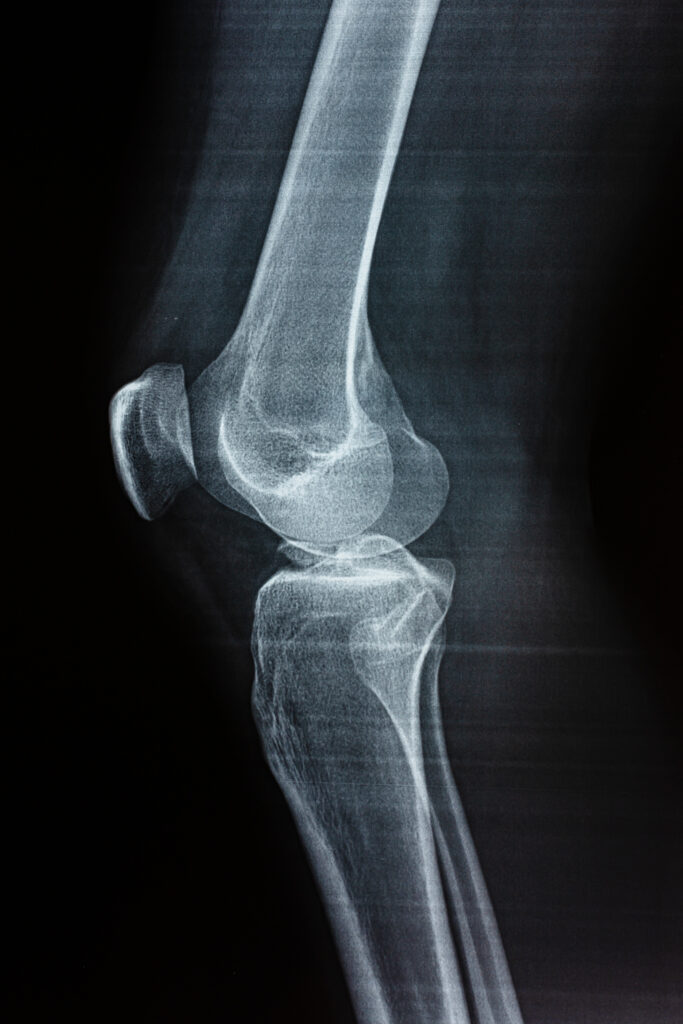

Hearing or feeling a pop from your knee can be unsettling. Many causes are harmless, but some require assessment and directed treatment. We describe how we decide when to watch, when to try nonoperative care, and when surgery may be appropriate.

Popping may be painless or associated with pain, swelling, instability, or loss of function. The pattern of symptoms and your history guide testing and treatment choices.

Several structures can produce popping sounds. The list below groups common causes with brief explanations and typical features to help you tell them apart.